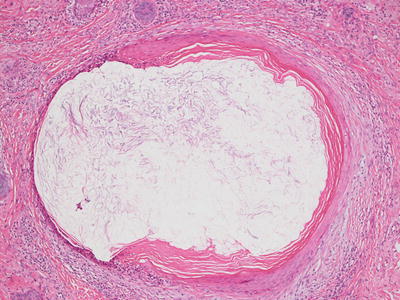

The histologic findings in acne conglobata are shared with those seen in other conditions including hidradenitis suppurativa. There is marked follicular plugging resulting in multiple follicular cysts that can be quite large (Fig. 10.9). These cysts are surrounded by dense inflammation including lymphocytes, neutrophils, and often granulomas with abundant multinucleated giant cells. As a result of repeated rupture of follicular cysts, there is extensive dermal scarring and even sinus tract formation (Fig. 10.10).

Fig. 10.9

Acne conglobata shows marked distortion of pilosebaceous units with dense scar formation

Fig. 10.10

Abundant pilosebaceous units are disrupted and surrounded by dense scarring throughout the dermis in acne conglobata